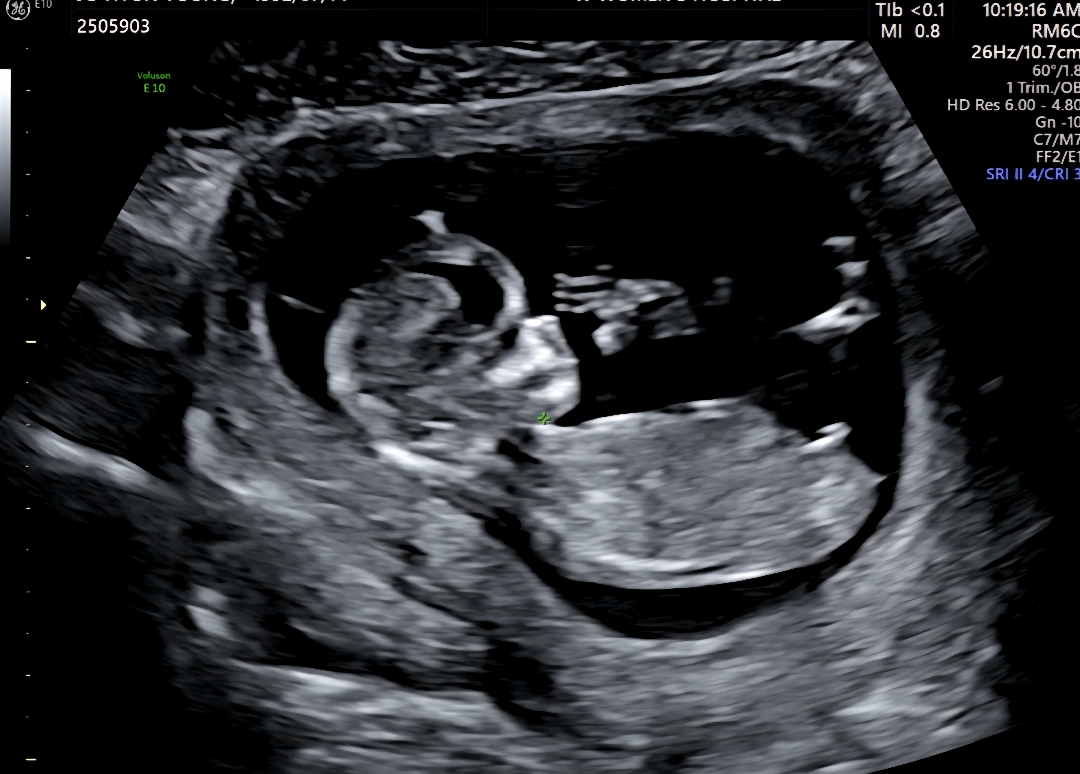

오늘 1차기형아 검사하고 왔어용~ 각도법으로 성별 구분 하시는 분들도 계신다해서 궁금한 마음에 올려봐요~ㅎㅎ

각도법으로 성별 봐주실분 계신가용?